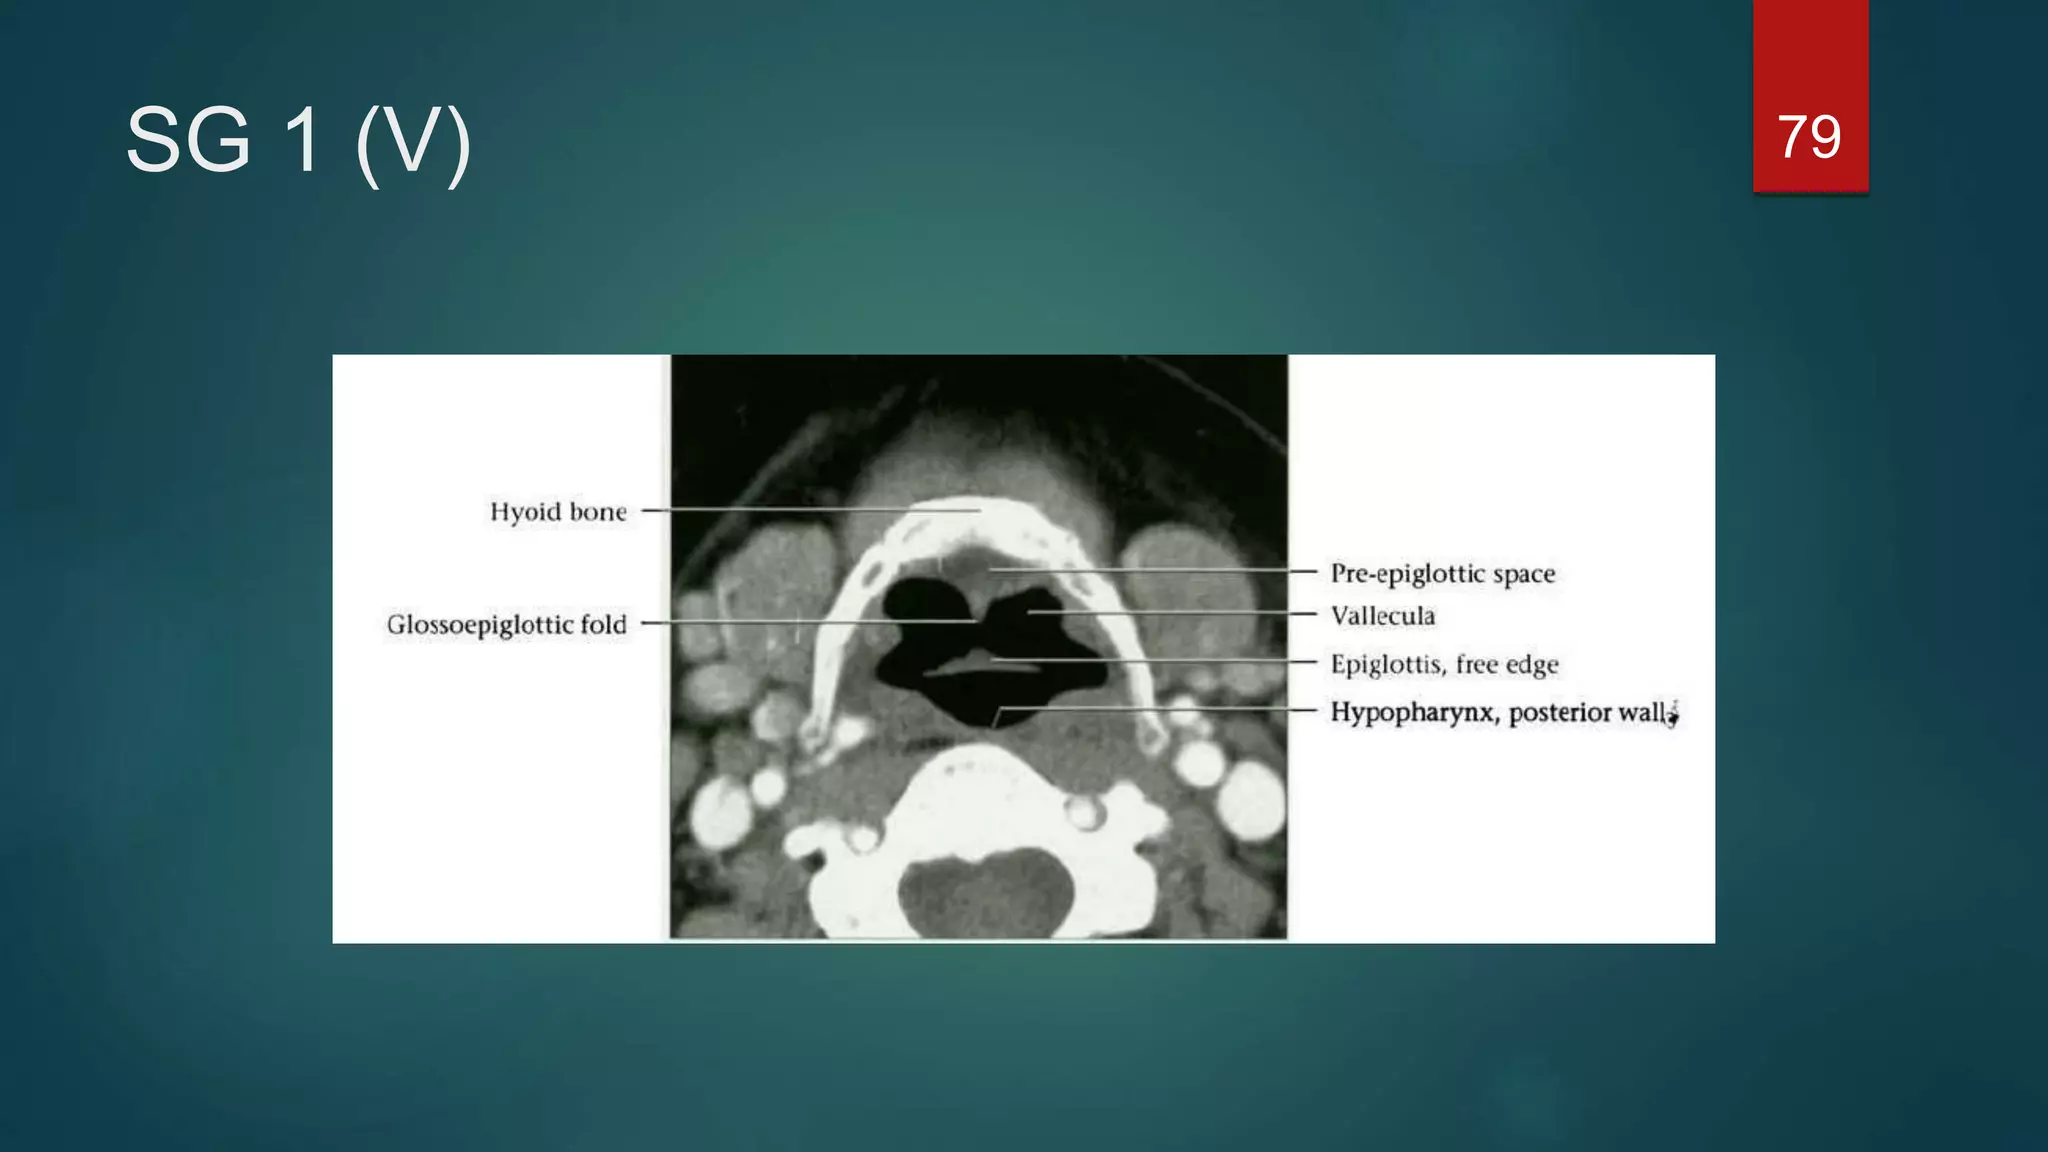

Cross-sectional anatomy of the

larynx

Supraglottic level

 The larynx is anterior to the piriform

sinuses, separated from them by the

aryepiglottic folds.

79SG 1 (V)

Cross-sectional anatomy ofthe larynx Supraglottic level  The larynx is anterior to the piriform sinuses, separated from them by the aryepiglottic folds. 71